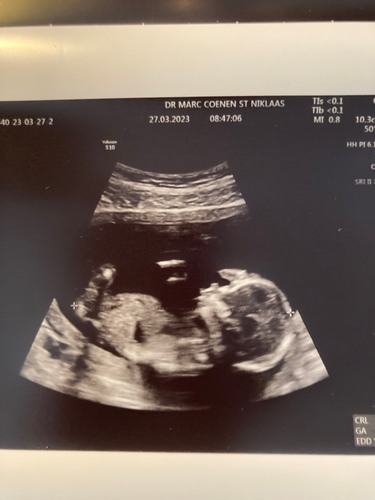

Kijk eens wat ze in t ziekenhuis voor elkaar hebben gekregen! Een hele mooie 3d echo met 13 weken!

Wauwww, bijzonder ❤️

Ohhhhh 🤩 wat mooi om te zien! Bijzonder hè 3D echo! Kan nu niet wachten tot wij ook weer mogen! Nog 7 weken aftellen en dan de 3D/4D pret echo! Dank voor het delen!